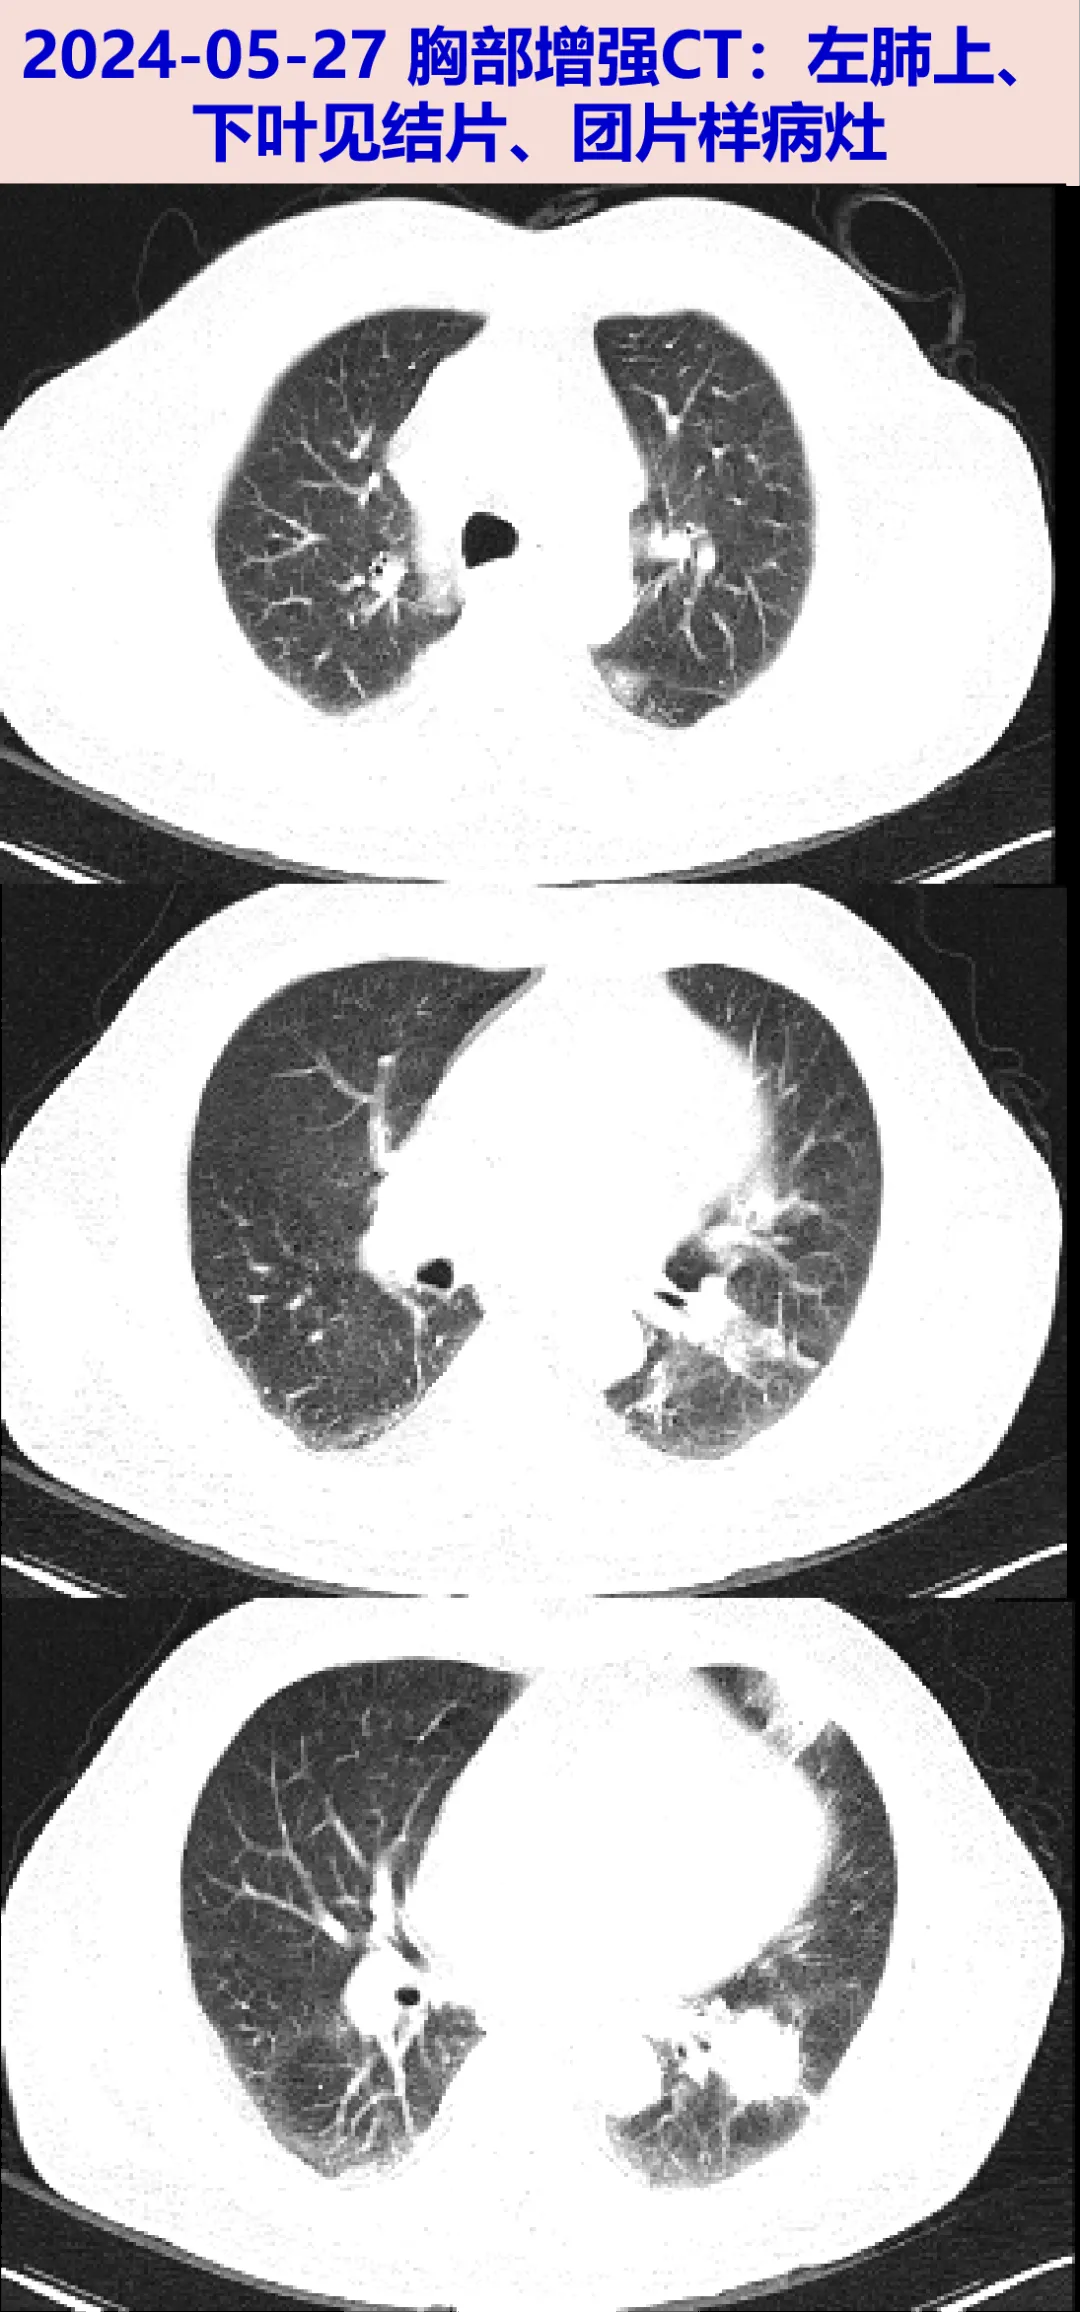

2024-05-27至我院就诊,行胸部增强CT: 左肺结片灶,较外院CT相仿。为明确左肺病灶性质收入我科。